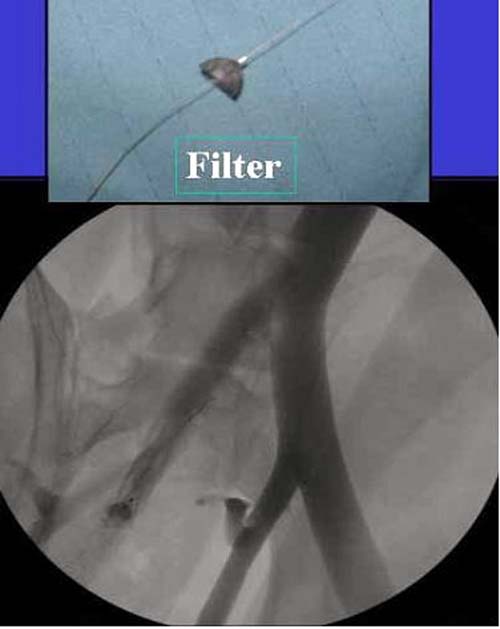

Профилактике тромвоза уделяем очень серьезное внимание в лечении травматических больных, особенно с политравмой - множественными переломами конечностей в сочетании с травмой живота, грудной клетки и больных "вскормленных продуктами МасДональдс" с повышенным весом, из-за их неподвижности.

Работаем вместе с хирургами-травматологами (в штатах все травмированные больные поступают, как больные хирургической службы, ортопед выступает в качестве консультанта), т.е. мы даем рекомендации о проведении профилактики тромбоза, совместно решаем о проведении фильтра - вена кава фильтр (см. приложение).

Если вена кава фильтр, хирурги проводят эту процедуру, а медикаментозную профилактику назначаем сами.

Из лекарств: Lovenox, Heparin, Arixtra, Fragmin, каждый на свое усмотрение, почему-то общие хирурги предпочитают гепарин, хотя за последнее 6-7 лет кому не лень проводили исследования профилактики тромбоза, но к консенсусу не пришли, ортопеды-травматологи - Lovenox, Hip and knee reconstructive Surgeons - Arixtra, персонально считаю - кто с чем работает, тем и пользуются.

Продолжения антикоагулянта до условной активности больного, если больной самостоятельно передвигается с помощью костылей, считаю, можно решить о прекращении профилактики.